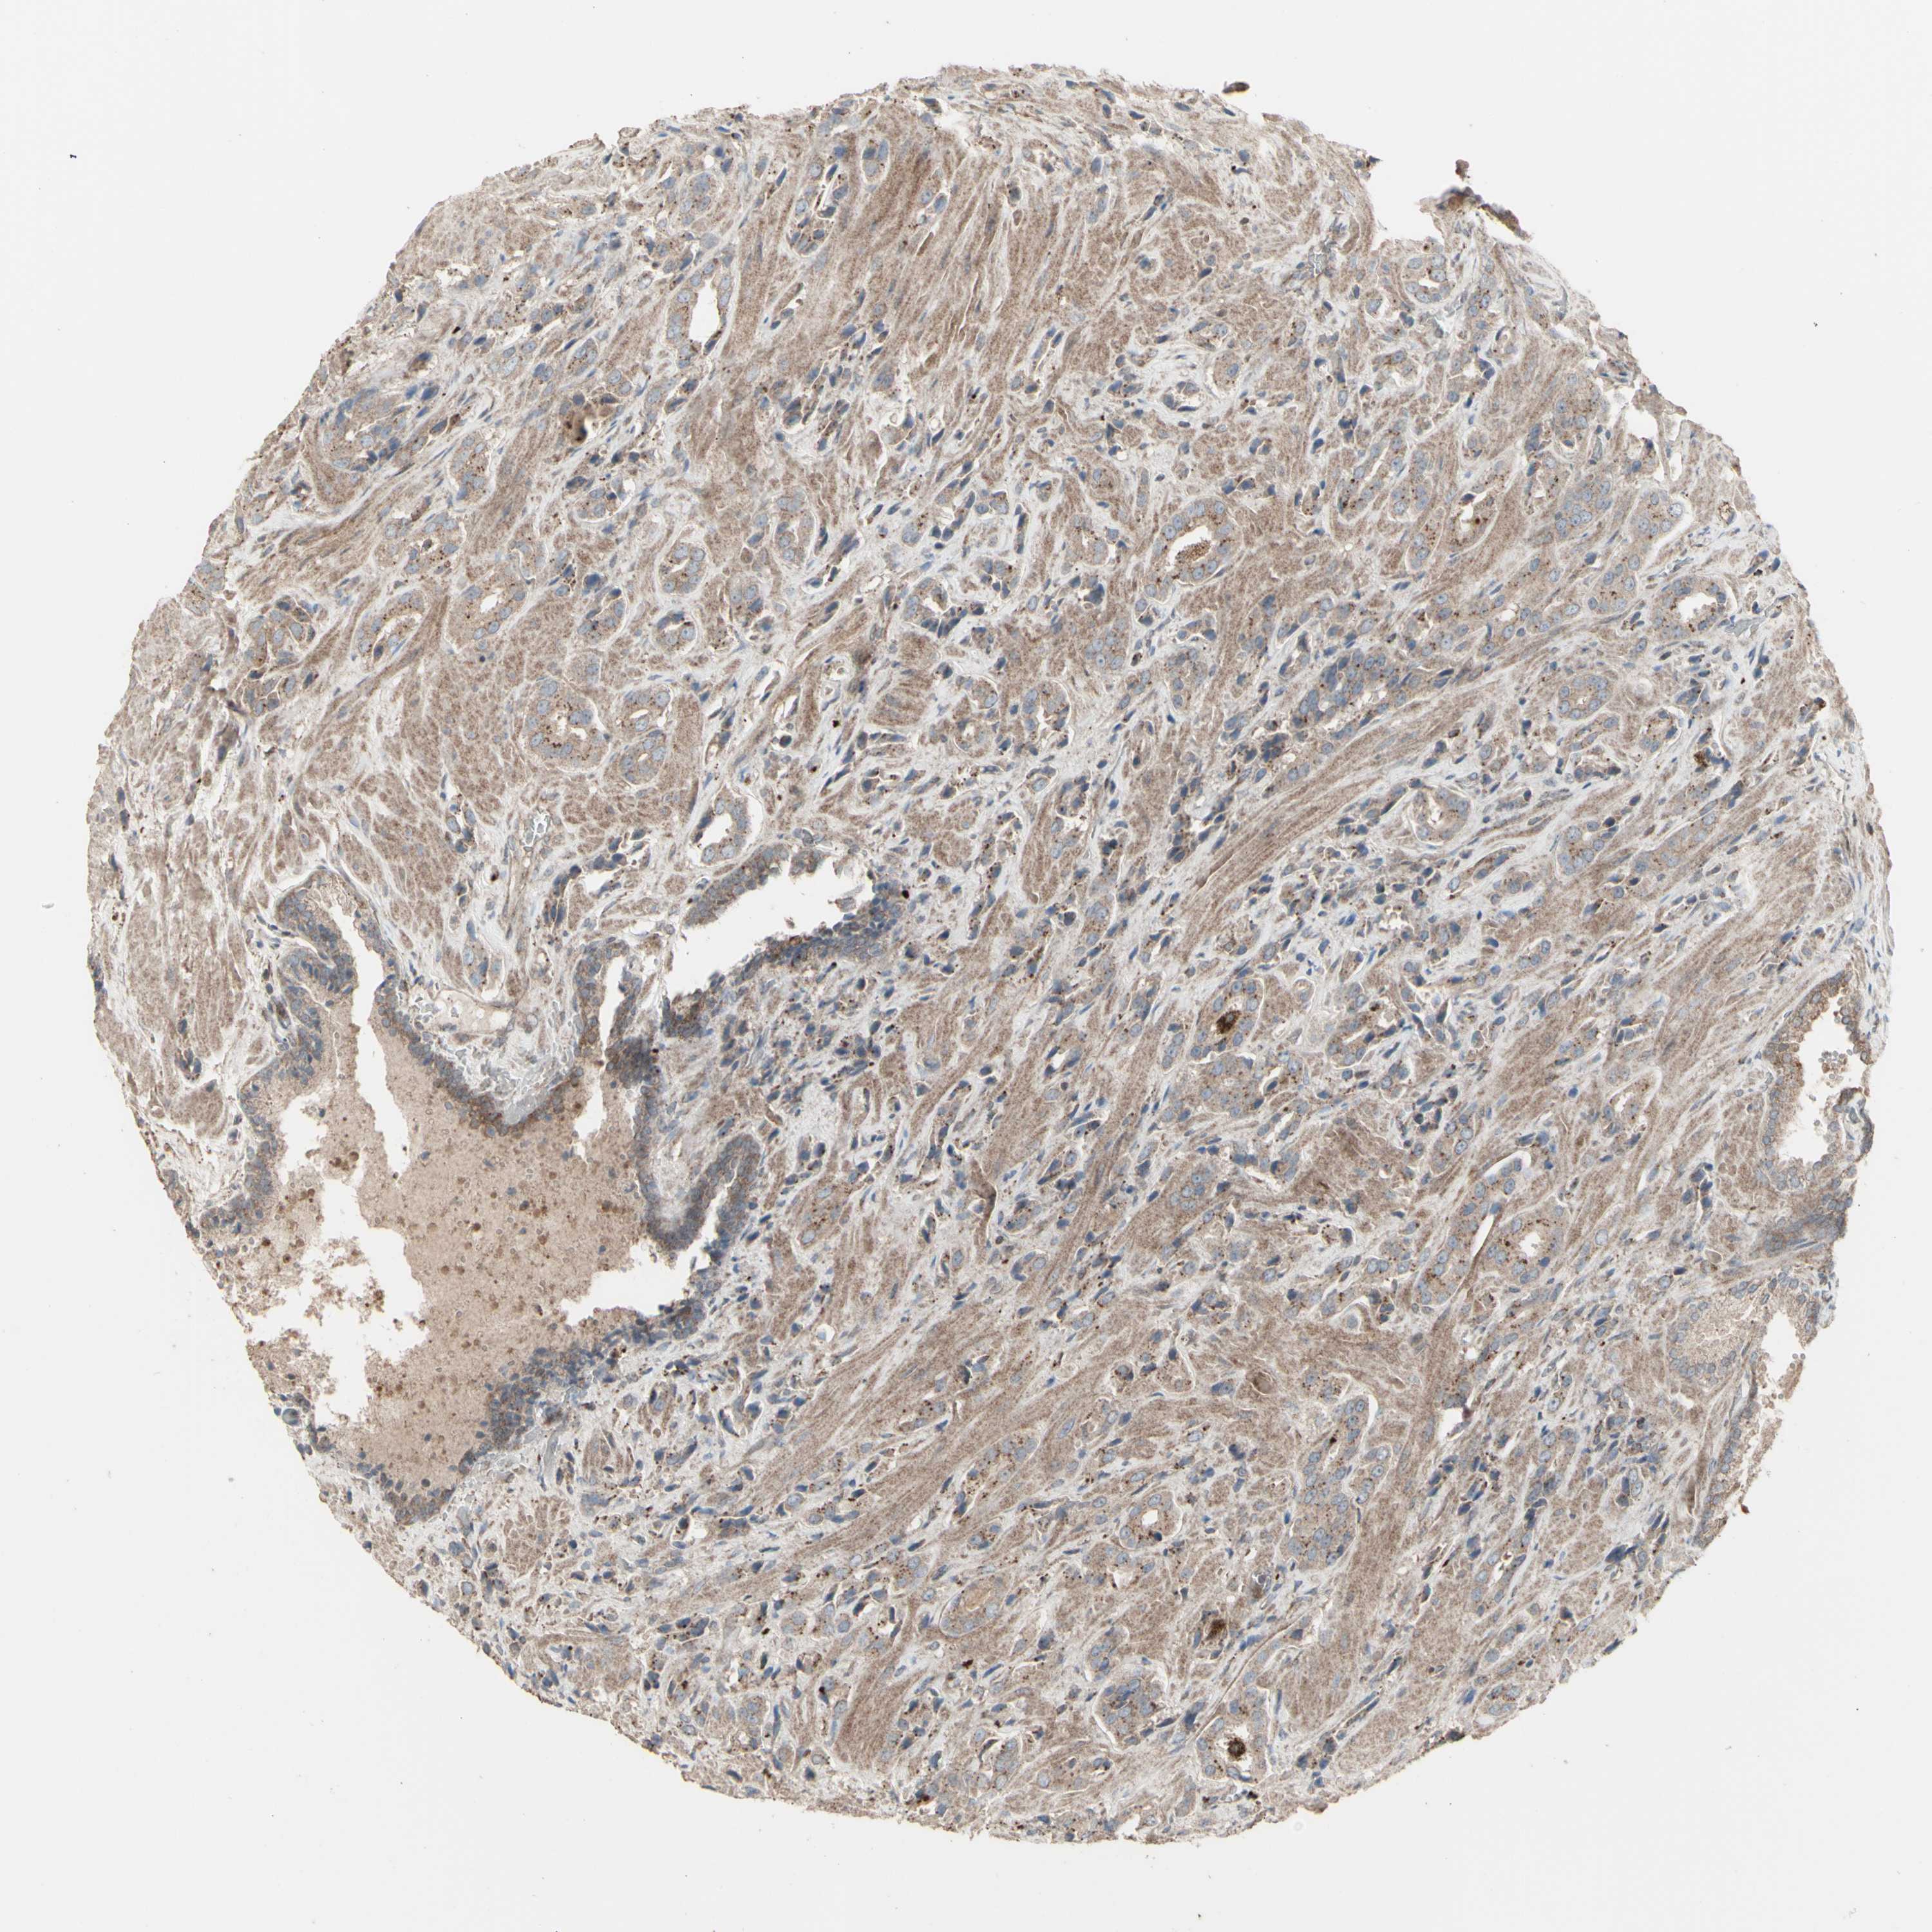

PROSTATE CANCER - Protein expressioni

A mouse-over function shows sample information and annotation data. Click on an image to view it in a full screen mode. Samples can be filtered based on level of antibody staining by selecting one or several of the following categories: high, medium, low and not detected. The assay and annotation is described here.

Antibody stainingi

Antibody staining in the annotated cell types in the current human tissue is reported as not detected, low, medium, or high, based on conventional immunohistochemistry profiling in selected tissues. This score is based on the combination of the staining intensity and fraction of stained cells.

Each image is clickable and will lead to virtual microscopy that enables deeper exploration of all samples and also displays staining intensity scores, fraction scores and subcellular localization as well as patient and tissue information for each sample.

Antibody HPA002633

Antibody HPA046758

Antibody CAB010906

Staining

High

Medium

Low

Not detected

Intensity

Strong

Moderate

Weak

Negative

Quantity

>75%

75%-25%

<25%

None

Location

Nuclear

Cytoplasmic/membranous

Cytoplasmic/membranous,nuclear

Adenocarcinoma, Medium grade

Adenocarcinoma, High grade

Adenocarcinoma, Low grade

Adenocarcinoma, NOS